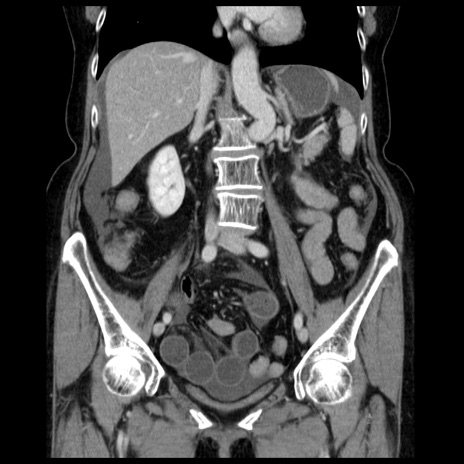

症例13(冠状断像)

【症例】70歳代女性

【主訴】腹痛、嘔吐

【現病歴】15時間程前(昨晩)より腹痛あり。今朝になっても症状の改善なく、嘔吐あり。腹痛も増悪あり、救急外来受診。

【既往歴】子宮癌全摘術後

【身体所見】意識清明、BP 121/72mmHg、P 74bpm、SpO2 100%(RA)、腹部:平坦・軟、腸雑音ほぼ聴取せず。下腹部・心窩部・臍左上に圧痛あり。反跳痛なし。

【データ】WBC 10600、CRP 0.15